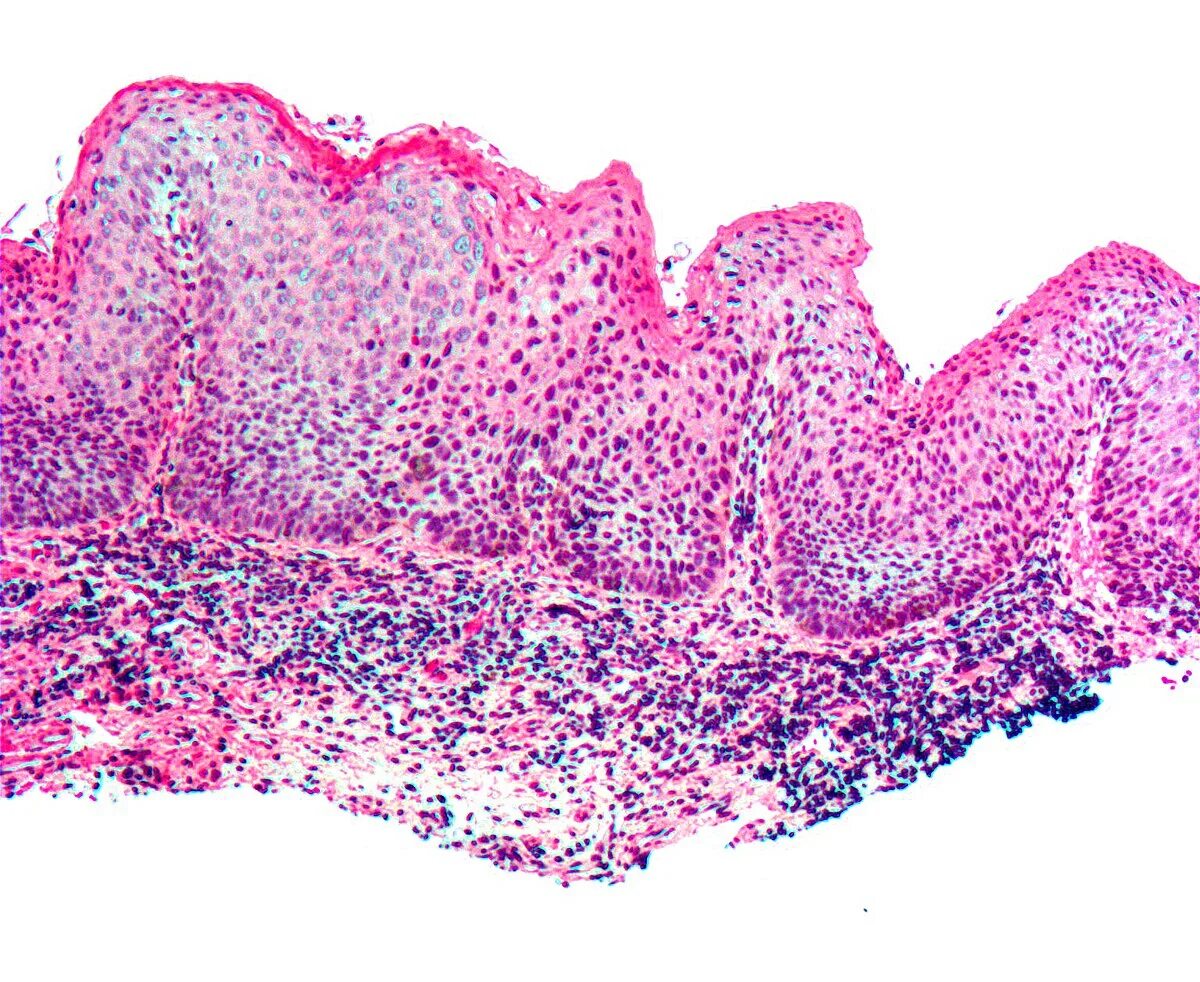

Выраженная атипия